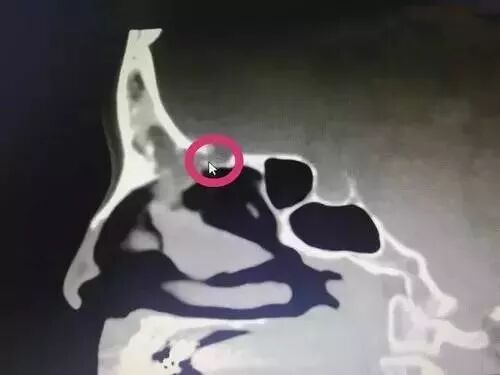

画红圈处就是破裂的小洞

鼻子由鼻腔和4对鼻窦组成,结构像一个“四室一厅”的房子,刘阿姨患有多年的慢性鼻窦炎,并且是全组副鼻窦(即额窦、筛窦、蝶窦、上颌窦)炎症,鼻窦中充满了脓液,像“滴水穿石”般长期侵蚀导致了骨质破损,从而加速颅内感染和扩散,影响中枢神经系统并造成左侧肢体瘫痪。